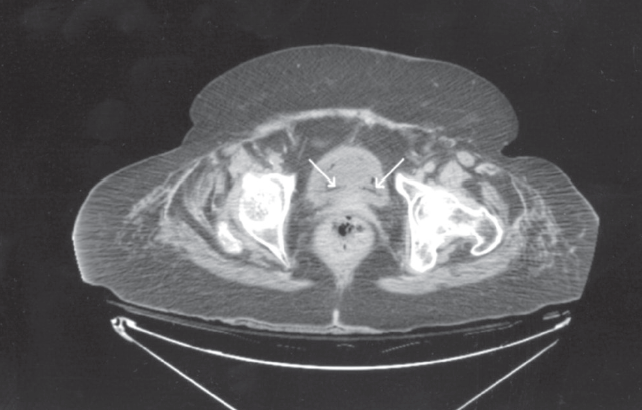

Laboratory testing. White blood cell count was 9820/µL, blood glucose level was 286 mg/dL, and her glycosylated hemoglobin was 7.1%. Urinalysis findings were consistent with urinary tract infection (UTI). A CT scan of the abdomen revealed air within the wall of the urinary bladder, compatible with emphysematous cystitis. Because of the patient’s age and comorbidities, she was empirically treated with piperacillin/tazobactam. Blood cultures were negative. Urine culture later grew Escherichia coli.

Discussion. Emphysematous cystitis is a commonly missed, relatively unknown disease. Although the pathogenesis of the gas formation is still unclear, metabolism of glucose and albumin in the urine by gas-forming organisms and impaired host response with poor vascular perfusion are 2 postulated theories.1-4 E coli and pneumoniae are commonly isolated; however, other organisms, such as Clostridium, Pseudomonas, Proteus, Enterococcus, Aspergillus, and Candida, have been reported.2 Risk factors include female gender, diabetes mellitus, age older than 60 years, debilitated states, neurogenic bladder, recurrent UTI, urinary stasis secondary to bladder outlet obstruction, alcoholism, and malnutrition.1

When intraluminal gas is present, other entities, such as a recent urinary tract instrumentation, trauma, and vesicocolic/vesicovaginal fistulas, should also be considered.2,4,5 Clinical presentations range from no symptoms, descriptive pneumaturia, and irritative voiding symptoms to acute abdomen and severe sepsis.2,3 Thus, a high index of suspicion for emphysematous cystitis is required. The condition is usually diagnosed incidentally by plain abdominal film, ultrasonography, or CT scan findings. Other modalities include direct visualization during cystoscopy or laparotomy and biopsy. 2,3

However, CT remains the preferred diagnostic method, because of its high sensitivity and specificity in detecting gas and the extent and severity of disease and in differentiating other causes of intraluminal gas formation.1,2,5